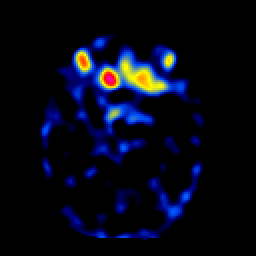

SPECT TL Study #2 -- Slice #20

[Home][Help][Clinical][Tour 1][Tour 2][Tour 3] Slice 20